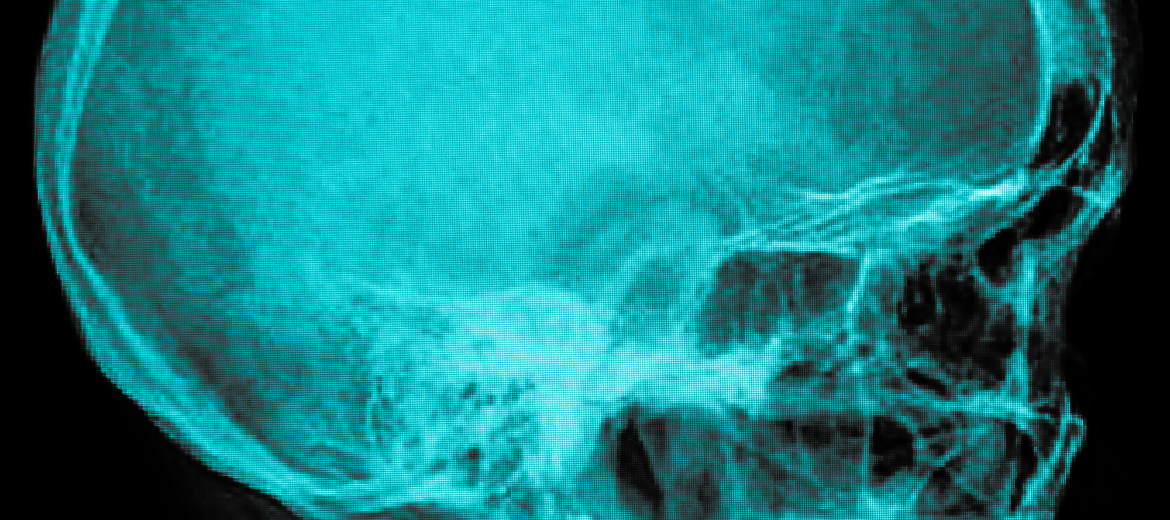

Hackettstown – The practice has established The Concussion Center at The Orthopedic Institute of New Jersey. The goal at The Center is to educate, provide baseline testing, diagnose and treat patients who may have suffered a concussion. In recent years, a strong focus has been placed on the prevention and treatment of concussions. Many parents and athletes have been appropriately concerned about participating in sports, particularly those sports that have a higher potential for head injuries. Among professional sports, a week rarely passes without an incident, lawsuit, or significant concern related to concussions and concussive care and testing. As more people become aware of the topic, better preventative care, treatment and proper plans for returning to action are being put in place and athletes should be taking advantage of this. We believe that through the Concussion Center at our Practice, we can assist our patients to become better educated about this condition and provide them with state-of-the- art care. The medical evaluation of a concussion can be extremely complex because concussive injuries can affect many different parts of the brain. The development of computerized neuropsychological or baseline testing has become a very useful tool to evaluate an athlete’s memory, concentration and reaction times. Computerized neuropsychological testing does not replace or eliminate the need for a specialized doctor evaluation but it helps to standardize and simplify the return to play process. Athletes at any level who are tested before a season begins can establish a baseline related to his or her cognitive functioning. If during the course of athletic participation an athlete suffers a possible concussion, they can then be retested to determine if there are any deficits. Appropriate care can then follow. Neuropsychological/BaselineTesting is conducted at The Orthopedic Institute of New Jersey by appointment. No athlete, coach or parent should ever consider a concussion to be an insignificant event. The majority of serious brain injuries related to a concussion occur when an athlete suffers repeat head trauma while still symptomatic from an undiagnosed concussion. Only a trained medical professional can evaluate a concussion and in New Jersey, only a physician with specialized concussion training can diagnose or rule out a concussion.